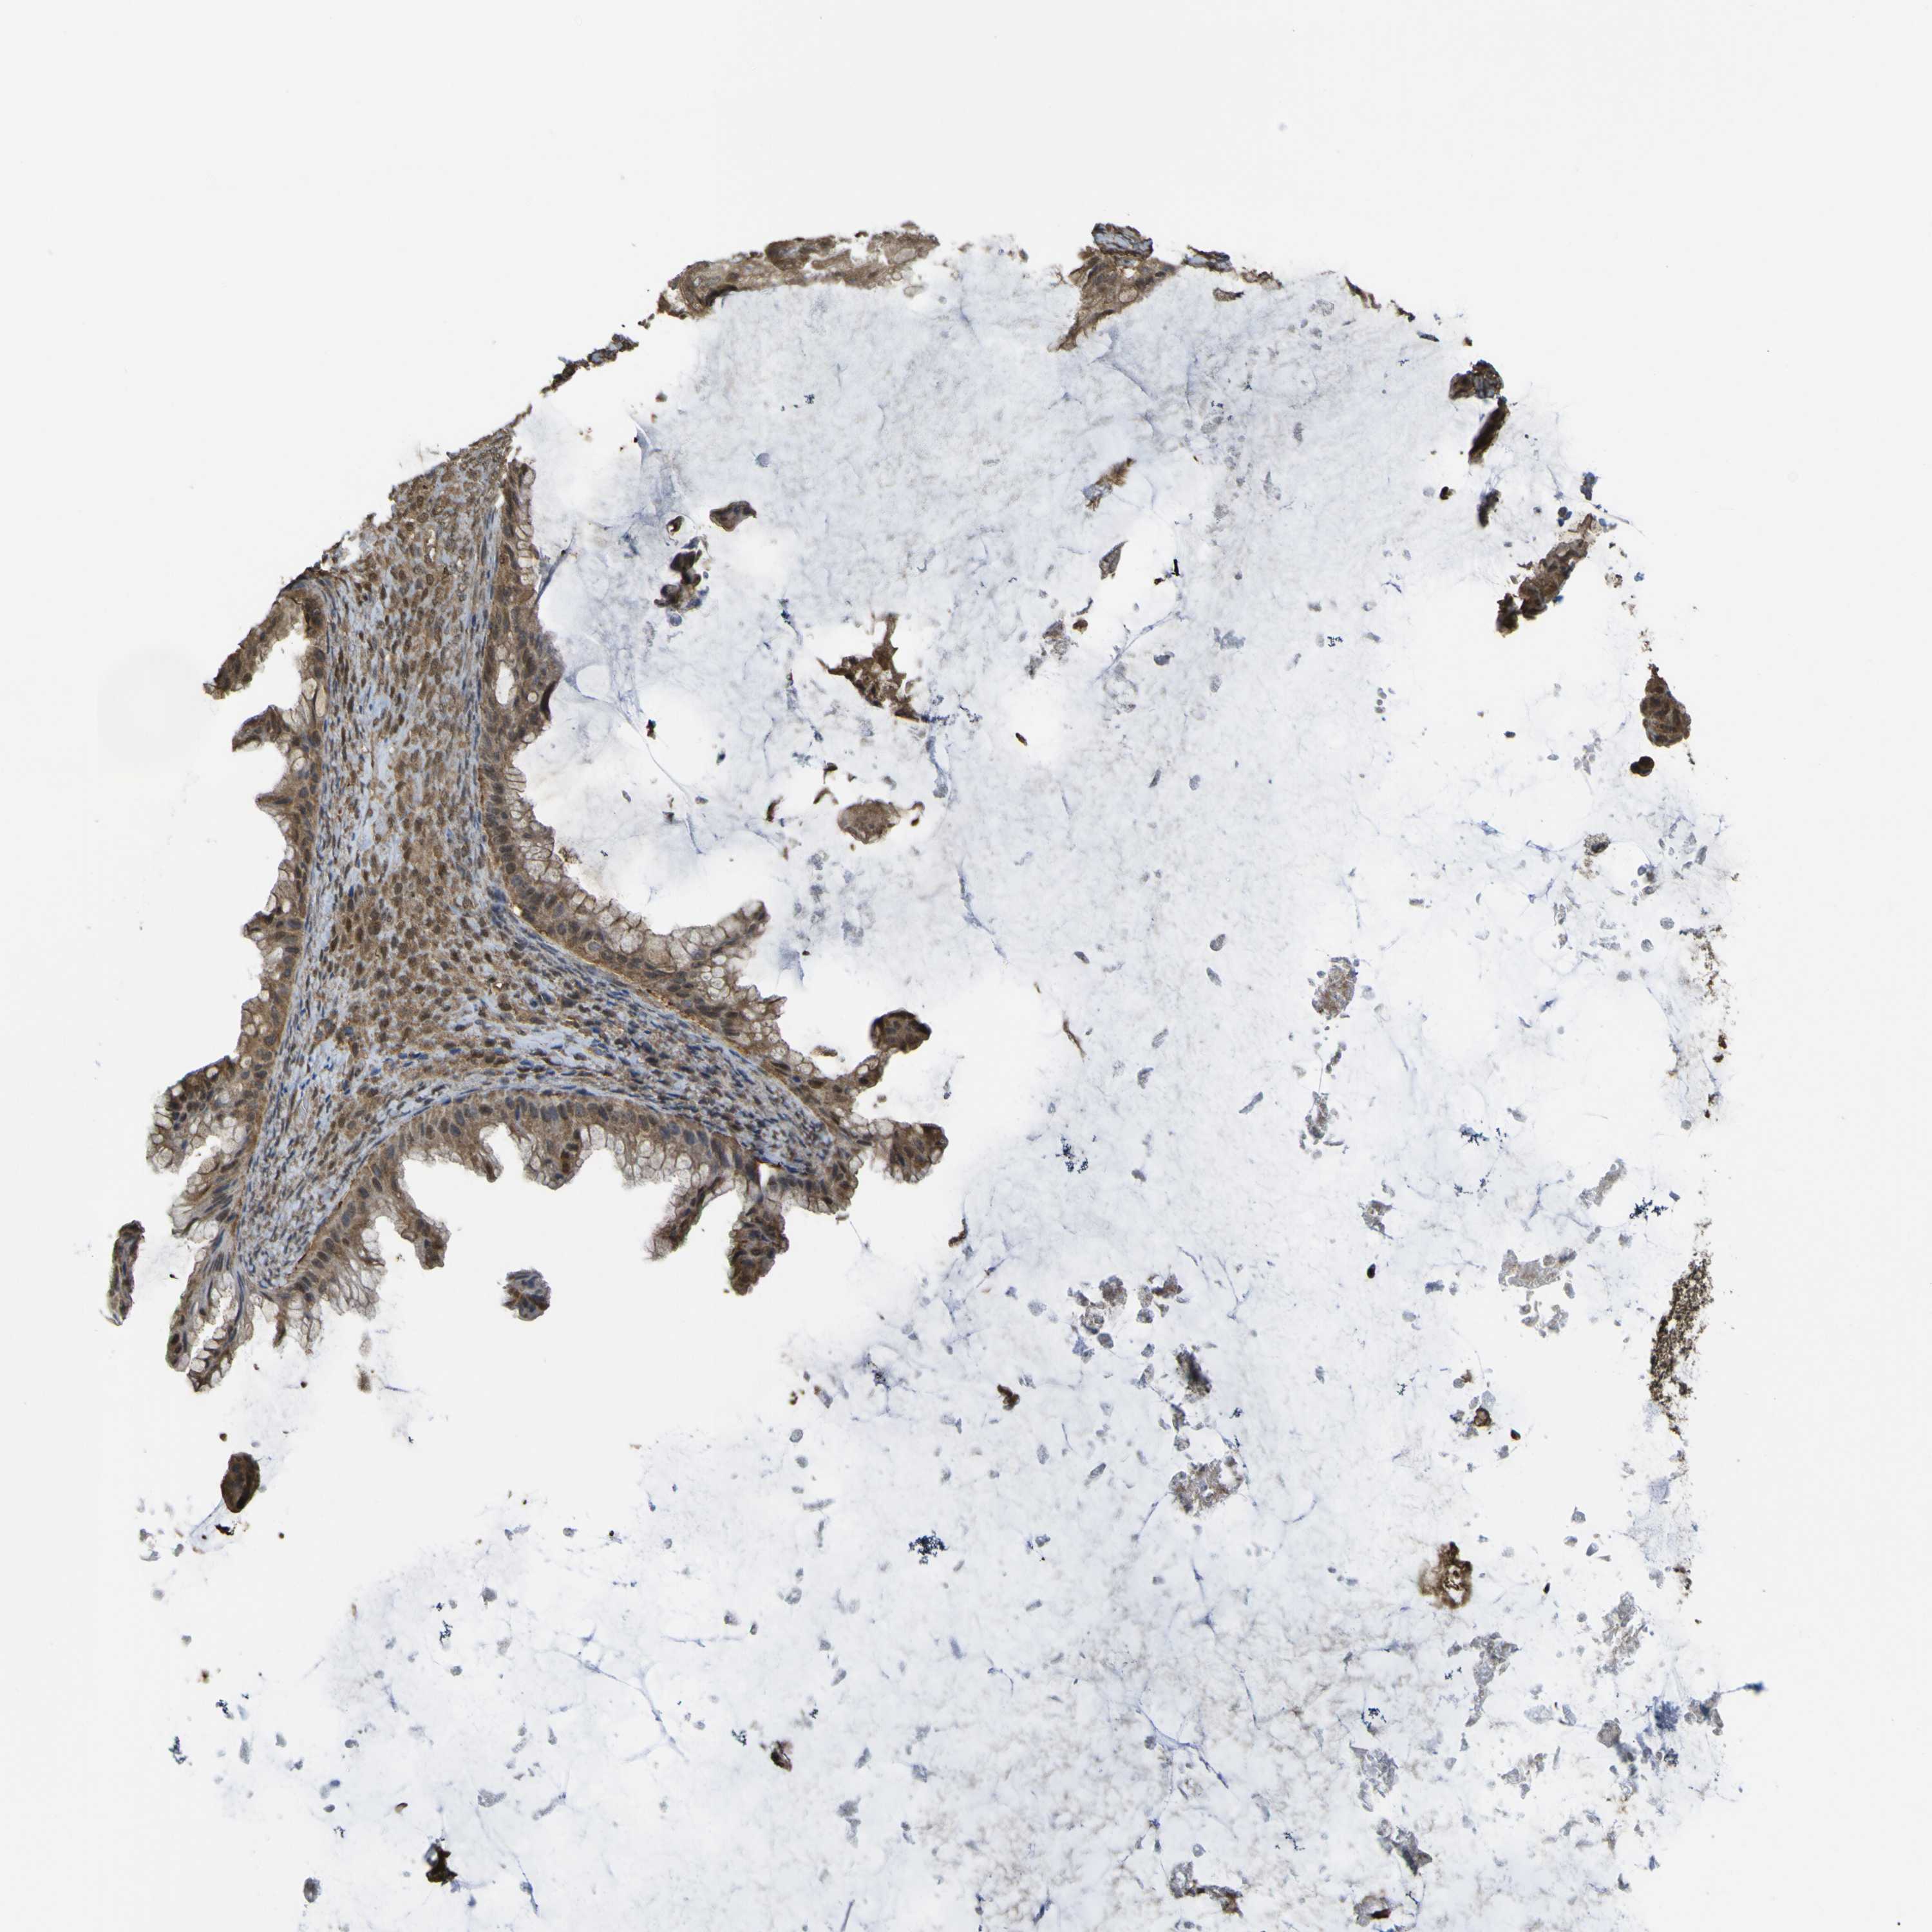

OVARIAN CANCER - Protein expressioni

A mouse-over function shows sample information and annotation data. Click on an image to view it in a full screen mode. Samples can be filtered based on level of antibody staining by selecting one or several of the following categories: high, medium, low and not detected. The assay and annotation is described here.

Note that samples used for immunohistochemistry by the Human Protein Atlas do not correspond to samples in the TCGA dataset.

Antibody stainingi

Antibody staining in the annotated cell types in the current human tissue is reported as not detected, low, medium, or high, based on conventional immunohistochemistry profiling in selected tissues. This score is based on the combination of the staining intensity and fraction of stained cells.

Each image is clickable and will lead to virtual microscopy that enables deeper exploration of all samples and also displays staining intensity scores, fraction scores and subcellular localization as well as patient and tissue information for each sample.

Antibody HPA026918

Antibody CAB013274

Antibody CAB018389

Staining

High

Medium

Low

Not detected

Cystadenocarcinoma, mucinous, NOS